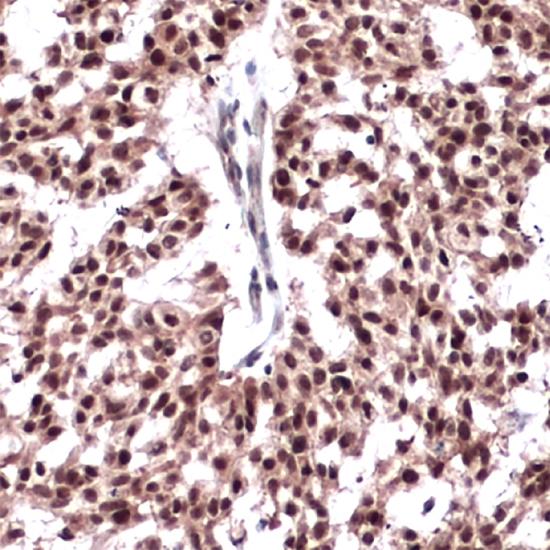

ER-Beta抗體試劑(免疫組織化學(xué)) 閩廈械備20180200號(hào)

• 預(yù)處理:

熱修復(fù)

• 陽(yáng)性部位:

細(xì)胞核

• 陽(yáng)性對(duì)照:

乳腺癌

• 適用組織:

石蠟

• 免疫顯色試劑:

iVision?

• 產(chǎn)品編號(hào):

AM0352

• 種屬來(lái)源:

鼠單抗

• 克隆號(hào):

EMR02

雌激素受體(ER)存在兩種類型:α和β,兩者結(jié)構(gòu)相似。ER-β在復(fù)雜的信號(hào)轉(zhuǎn)導(dǎo)途徑中是一個(gè)非常重要的元件,能特定地調(diào)節(jié)靶組織和腫瘤組織的生長(zhǎng)。ER-β在乳腺癌、卵巢癌、前列腺癌、結(jié)腸癌以及原發(fā)性肝癌組織中的表達(dá)發(fā)生特征性的變化,提示在這些腫瘤發(fā)生發(fā)展過(guò)程中ER-β起重要作用。